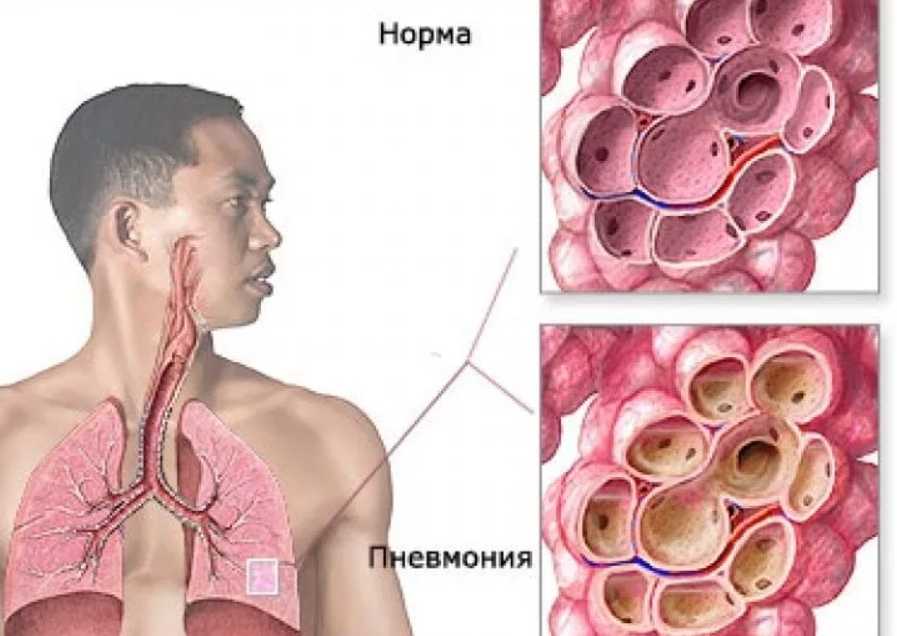

Коронавирус переходит в нижние дыхательные пути, поражает альвеолы легких. Начинается воспаление. Это нарушает газообмен, приводит к одышке. Даже после восстановления от пневмонии у человека может длительное время оставаться дыхательная недостаточность.

Пневмония при коронавирусе – распространенное явление. Причем многие болезненные симптомы могут быть незаметными. Проблема усложнена большим количеством очагов воспаления в легочной ткани с блокировкой альвеол легких. В данном случае необходима своевременная медицинская помощь.

- альвеолит;

Чтобы точно убедиться в наличии пневмонии без температуры, поставить точный диагноз, специалист выслушивает жалобы пациента, осматривает грудную клетку, проверяет симметричность дыхания. Прослушивание легких позволяет выявить хрипы, а больные участки во время простукивания издают приглушенный звук.